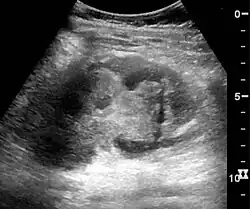

The kidney is divided into parenchyma and renal sinus. The renal sinus is hyperechoic and is composed of calyces, the renal pelvis, fat and the major intrarenal vessels. In the normal kidney, the urinary collecting system in the renal sinus is not visible, but it creates a heteroechoic appearance with the interposed fat and vessels. The parenchyma is more hypoechoic and homogenous and is divided into the outermost cortex and the innermost and slightly less echogenic medullary pyramids. Between the pyramids are the cortical infoldings, called columns of Bertin (Figure 1). In the pediatric patient, it is easier to differentiate the hypoechoic medullar pyramids from the more echogenic peripheral zone of the cortex in the parenchyma rim, as well as the columns of Bertin (Figure 2).[1]

Figure 1. Normal adult kidney. Measurement of kidney length on the US image is illustrated by '+' and a dashed line. *Column of Bertin; ** pyramid; *** cortex; **** sinus.[1]